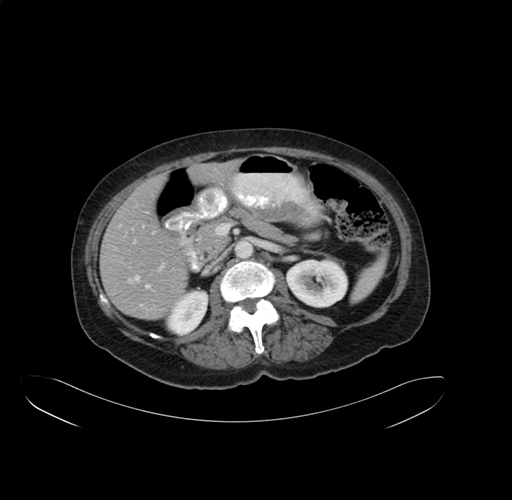

Axial Venous